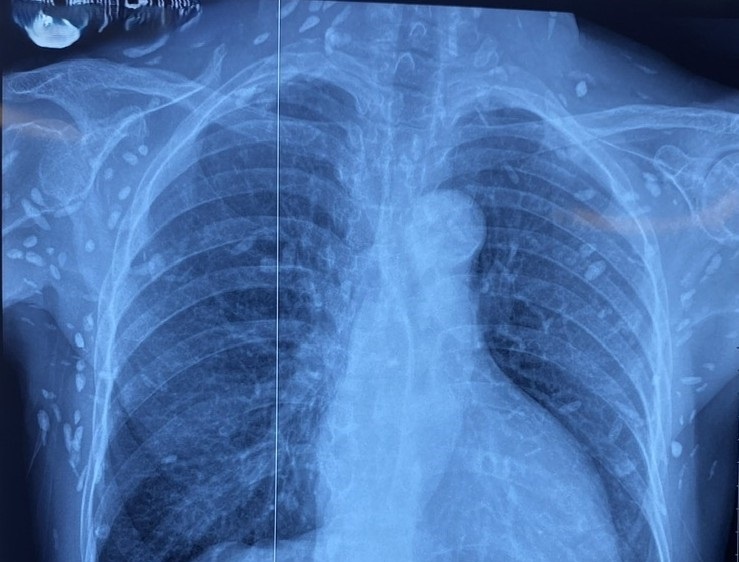

Nhiều nốt cản quang dưới da thành ngực - bụng và chi trên. Ảnh: BVCC.

Bệnh nhân được chuyển lên từ tuyến trước trong tình trạng rối loạn ý thức, đe dọa suy hô hấp. Kết quả chụp CT sọ não và X-quang ngực cho thấy nhiều nốt cản quang trong nhu mô não và dưới da vùng ngực - bụng, gợi ý tổn thương do sán dây lợn.

Theo ThS.BS Nguyễn Sỹ Thấu, khoa Hồi sức Truyền nhiễm, một số u cục nhỏ có thể sờ thấy dưới da vùng ngực và cánh tay của bệnh nhân. Dù xét nghiệm kháng thể IgM với sán dây lợn âm tính, hình ảnh X-quang cho thấy bệnh nhân đã từng nhiễm ấu trùng sán dây lợn, sau đó các nang sán thoái hóa, vôi hóa và tồn tại lâu dài trong mô.

Trong một số trường hợp, nang sán tự thoái hóa hoặc vôi hóa, để lại các nốt cản quang trên phim X-quang như trường hợp bệnh nhân nói trên.